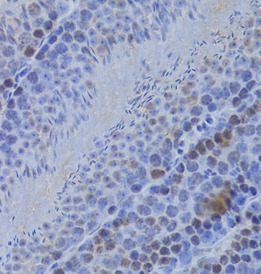

| 验证图片 | Immunohistochemistry of paraffin-embedded mouse testis using FNab03822(HELLS antibody) at dilution of 1:100 IP Result of anti-HELLS (IP:FNab03822, 4ug; Detection:FNab03822 1:1000) with mouse testis tissue lysate 4000ug. K-562 cells were subjected to SDS PAGE followed by western blot with FNab03822(HELLS antibody) at dilution of 1:1000 |